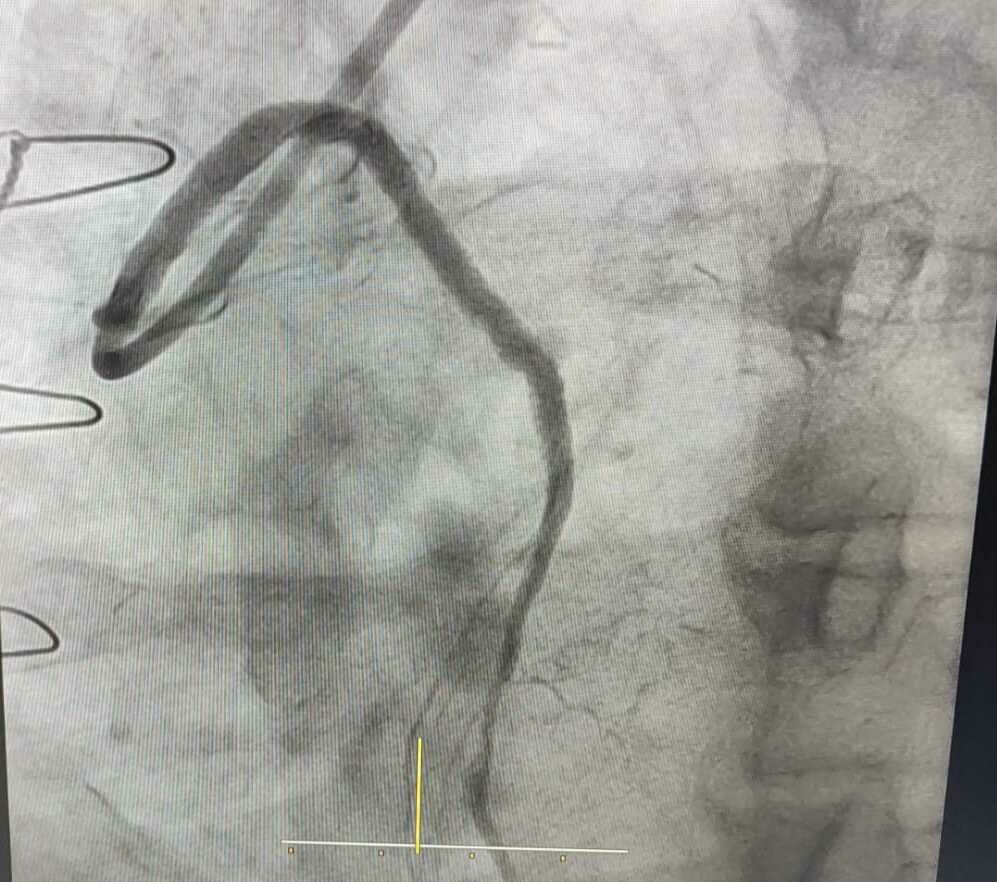

Complex Angioplasty - Dr Hasmukh Gujar Cardiologist

Dr. Hasmukh Gujar, a distinguished Cardiologist in Pune, recently demonstrated exemplary skill and compassion by performing a complex angioplas...